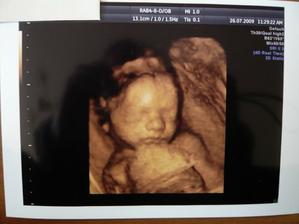

14.7.2009 jsme byli s taťkou na velkém UTZ (22+3) u pana MUDr. Břešťáka. Pan doktor byl fajn, ukázal nám miminka srdíčko, frekvenci srdíčka, tok krve do srdíčka a do aorty, játra, ledviny, močový měchýř..., dokonce i základy zoubků. Změřil všechny orgány a tělíčko a byl moc spokojený, vše je tak, jak má být. Nakonec nám potvrdil, že čekáme HOLČIČKU! Mrskala s sebou , chvíli trvalo, než pan doktor mohl změřit srdeční frekvenci. Vážíme 492g. Jsme s tatínkem moc šťastní, že je malá v pořádku. Dneska objednáme kočárek casualplay s4. Tak dneska 26.7.2009 jsme se byli s tatínkem podívat na naši holčičku na 4D UTZ. Udělali nám dvd a fotečku. Malá se nejdřív moc nechtěla ukazovat, schovávala se a točila se k nám zády. Pak si ale dala říct a krásně se nám ukázala. Je moc hezká, je to celý tatínek. Má jeho nosánek, pusinku, bradičku. Byla to sranda, zívla si a dala si nožičku k pusince, pak se pošťourala v oušku. A je to malá čertice, mrskala s sebou pěkně. Když jsme si jí doma prohlíželi na dvd, tak taťkovi dala pořádný kopanec, až vyskočil. 4D UTZ je fajn a my jsme spokojení. 4.8.2009 jsem byla na testu na cukrovce, ble. Ale nebylo to tak hrozný a máme splněno. 5.8.2009 jsme volali na vysledky jak nám cukrovka dopadla a výsledky jsou v pořádku, jupíí. Hnedka jsem to oslavila 2x koblihou a 2x croisantem. 11.8.2009 jsme byli na kontrole, malinká je v pořádku a je otočená hlavičkou dolů. Paní doktorka říkala, že je šikovná a že si myslí, že už takhle zůstane. Tak konečně uběhl měsíc a kousek a my se jdeme s taťkou podívat na naši holčičku. Paní doktorka říkala, že bude Michalku měřit, jsme totiž 32. týden. Paní doktorka malou změřila, odpovídáme úplně na den 31+3 a vážíme 1445g. Paní doktorka říkala, že Michalka je krásně proporční miminko, úplně podle tabulek a že by měla při porodu mít okolo 3500g. Michalka je moc šikovná, je stále hlavičkou dolů. Jupííí, jsme s tatínkem moc rádi. 01.10.2009 jsme byli u paní doktorky na další kontrole a Michalka se má dobře, krásně jí tlouklo srdíčko a je stále hlavičkou dolů, jupíí. Dostali jsme formulář na mateřskou a od 09.10.2009 na ní nastupujeme, jůůů, toto letí. Tak dneska je 13.10.2009 a byli jsme na poslední kontrole u naší paní doktorky, malá se má dobře, hlavičkou je stále dolů a váží 2300g, je to pěkný cvalík. Máme s tatínkem radost. CS máme 2. Už budeme chodit na kontroly do porodnici v Motole, kam se musíme objednat. 27.10.2009 jsem byla poprvé v poradně v Motole, paní doktorka nás vyšetřila, CS asi 4, pak jsme poslouchaly srdíčko naší malé princezny, zrovna cvičila spartakiádu. Kontrola v pořádku. Další kontrola bude i s monitorem, tak se moc těšíme. Dnes 03.11.2009 jsem byla v poradně v Motole, poprvé nám dělali monitor a malá se tak vrtěla, až mi sklouzla sonda a musela jsem si jí tam pak držet. Malá měla výsledky monitoru v pořádku, tak jsme moc s tatínkem rádi. Paní doktorka mě dnes nevyšetřovala, až zase na příští kontrole. Dneska je 10.11.2009, náš další den, kdy jsme se vydali do poradny. Natočili nám monitor, výsledky monitoru jsou v pořádku a paní doktorka mě i vyšetřila. CS 4, čípek zkrácený, měkký, hlavičkou je hezky nastavená. Je to naše malá šikulka a už se na ní s tatínkem móóc těšíme!!!